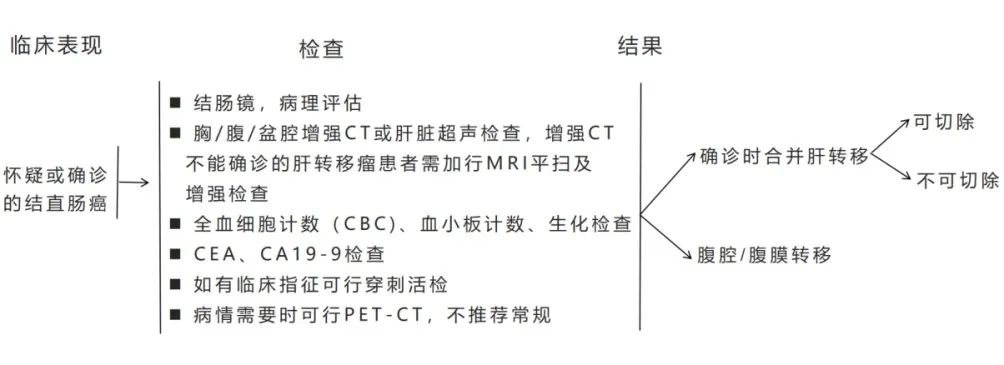

两年前,患者李女士被诊断为肠癌肝转移,先后尝试手术、化疗、生物治疗等多种治疗方式,但肝脏的病灶始终“不为所动”,并展现出一副“今日不将我消灭,明日必将汹涌而至”的态势。李女士辗转多处后至华山医院北院肿瘤科就诊,针对病灶残留,听从医生的建议决定使用“内放疗”。2个月前,梁晓华主任团队在李女士的肝病灶内成功植入了30枚碘125粒子,将病灶“团团包围”。患者术后未出现不适症状,并于隔日出院。术后2个月再次入院复查,肝内病灶明显缩小,逆转了肿瘤细胞“开疆拓土”的趋势。8Wz帝国网站管理系统

“内放疗”是一种放射性粒子植入术。医生利用现代影像学技术将具有放射性核素的粒子直接插植到肿瘤病灶内或肿瘤周围,放射性粒子通过持续释放射线对肿瘤细胞进行杀伤。“内放疗”属于高度适形放疗的一种,目前国内所应用的放射性粒子主要指碘125粒子。8Wz帝国网站管理系统

碘125粒子发出γ射线,该射线可以破坏肿瘤细胞核的DNA双链,导致DNA分子链的单链断裂或双键断裂,使肿瘤细胞失去繁殖能力; 射线还可以使机体内的水分子电离,产生自由基,该自由基与生物大分子相互作用,引起组织细胞的损伤,持续照射肿瘤细胞,使肿瘤的氧增比减少、乏氧细胞比例减少,不断地消耗肿瘤干细胞而使肿瘤细胞死亡。